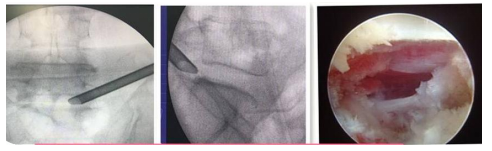

UBE(Unilateral Biportal Endscopic,單側(cè)雙通道內(nèi)鏡技術(shù))是新興的一種脊柱外科微創(chuàng)技術(shù),被廣泛應(yīng)用于脊柱退行性疾病(包括腰椎間盤(pán)突出癥、腰椎滑脫、腰椎管狹窄、頸椎病等)的治療,收到了較好的臨床效果。UBE手術(shù)具有視野清晰、創(chuàng)傷小、出血少、效率高、療效好及恢復(fù)快的特點(diǎn)。我院在重慶市較早開(kāi)展此項(xiàng)技術(shù),多次通過(guò)手術(shù)直播、學(xué)術(shù)講座和實(shí)操培訓(xùn)等形式充分展示此項(xiàng)技術(shù)。

利用椎間孔鏡從患者腰椎側(cè)方或者后方進(jìn)入達(dá)到椎間盤(pán)突出或者其他病變部位,用專(zhuān)用工具將突出(脫出)的椎間盤(pán)組織或病變?nèi)〕觯ㄈコ亩_(dá)到治療椎間盤(pán)突出或者椎管狹窄的目的。它的優(yōu)勢(shì)在于:局部麻醉、微創(chuàng)、切口小(僅約7mm),出血少,恢復(fù)快(第二天即可佩戴硬腰圍下地)及療效好。